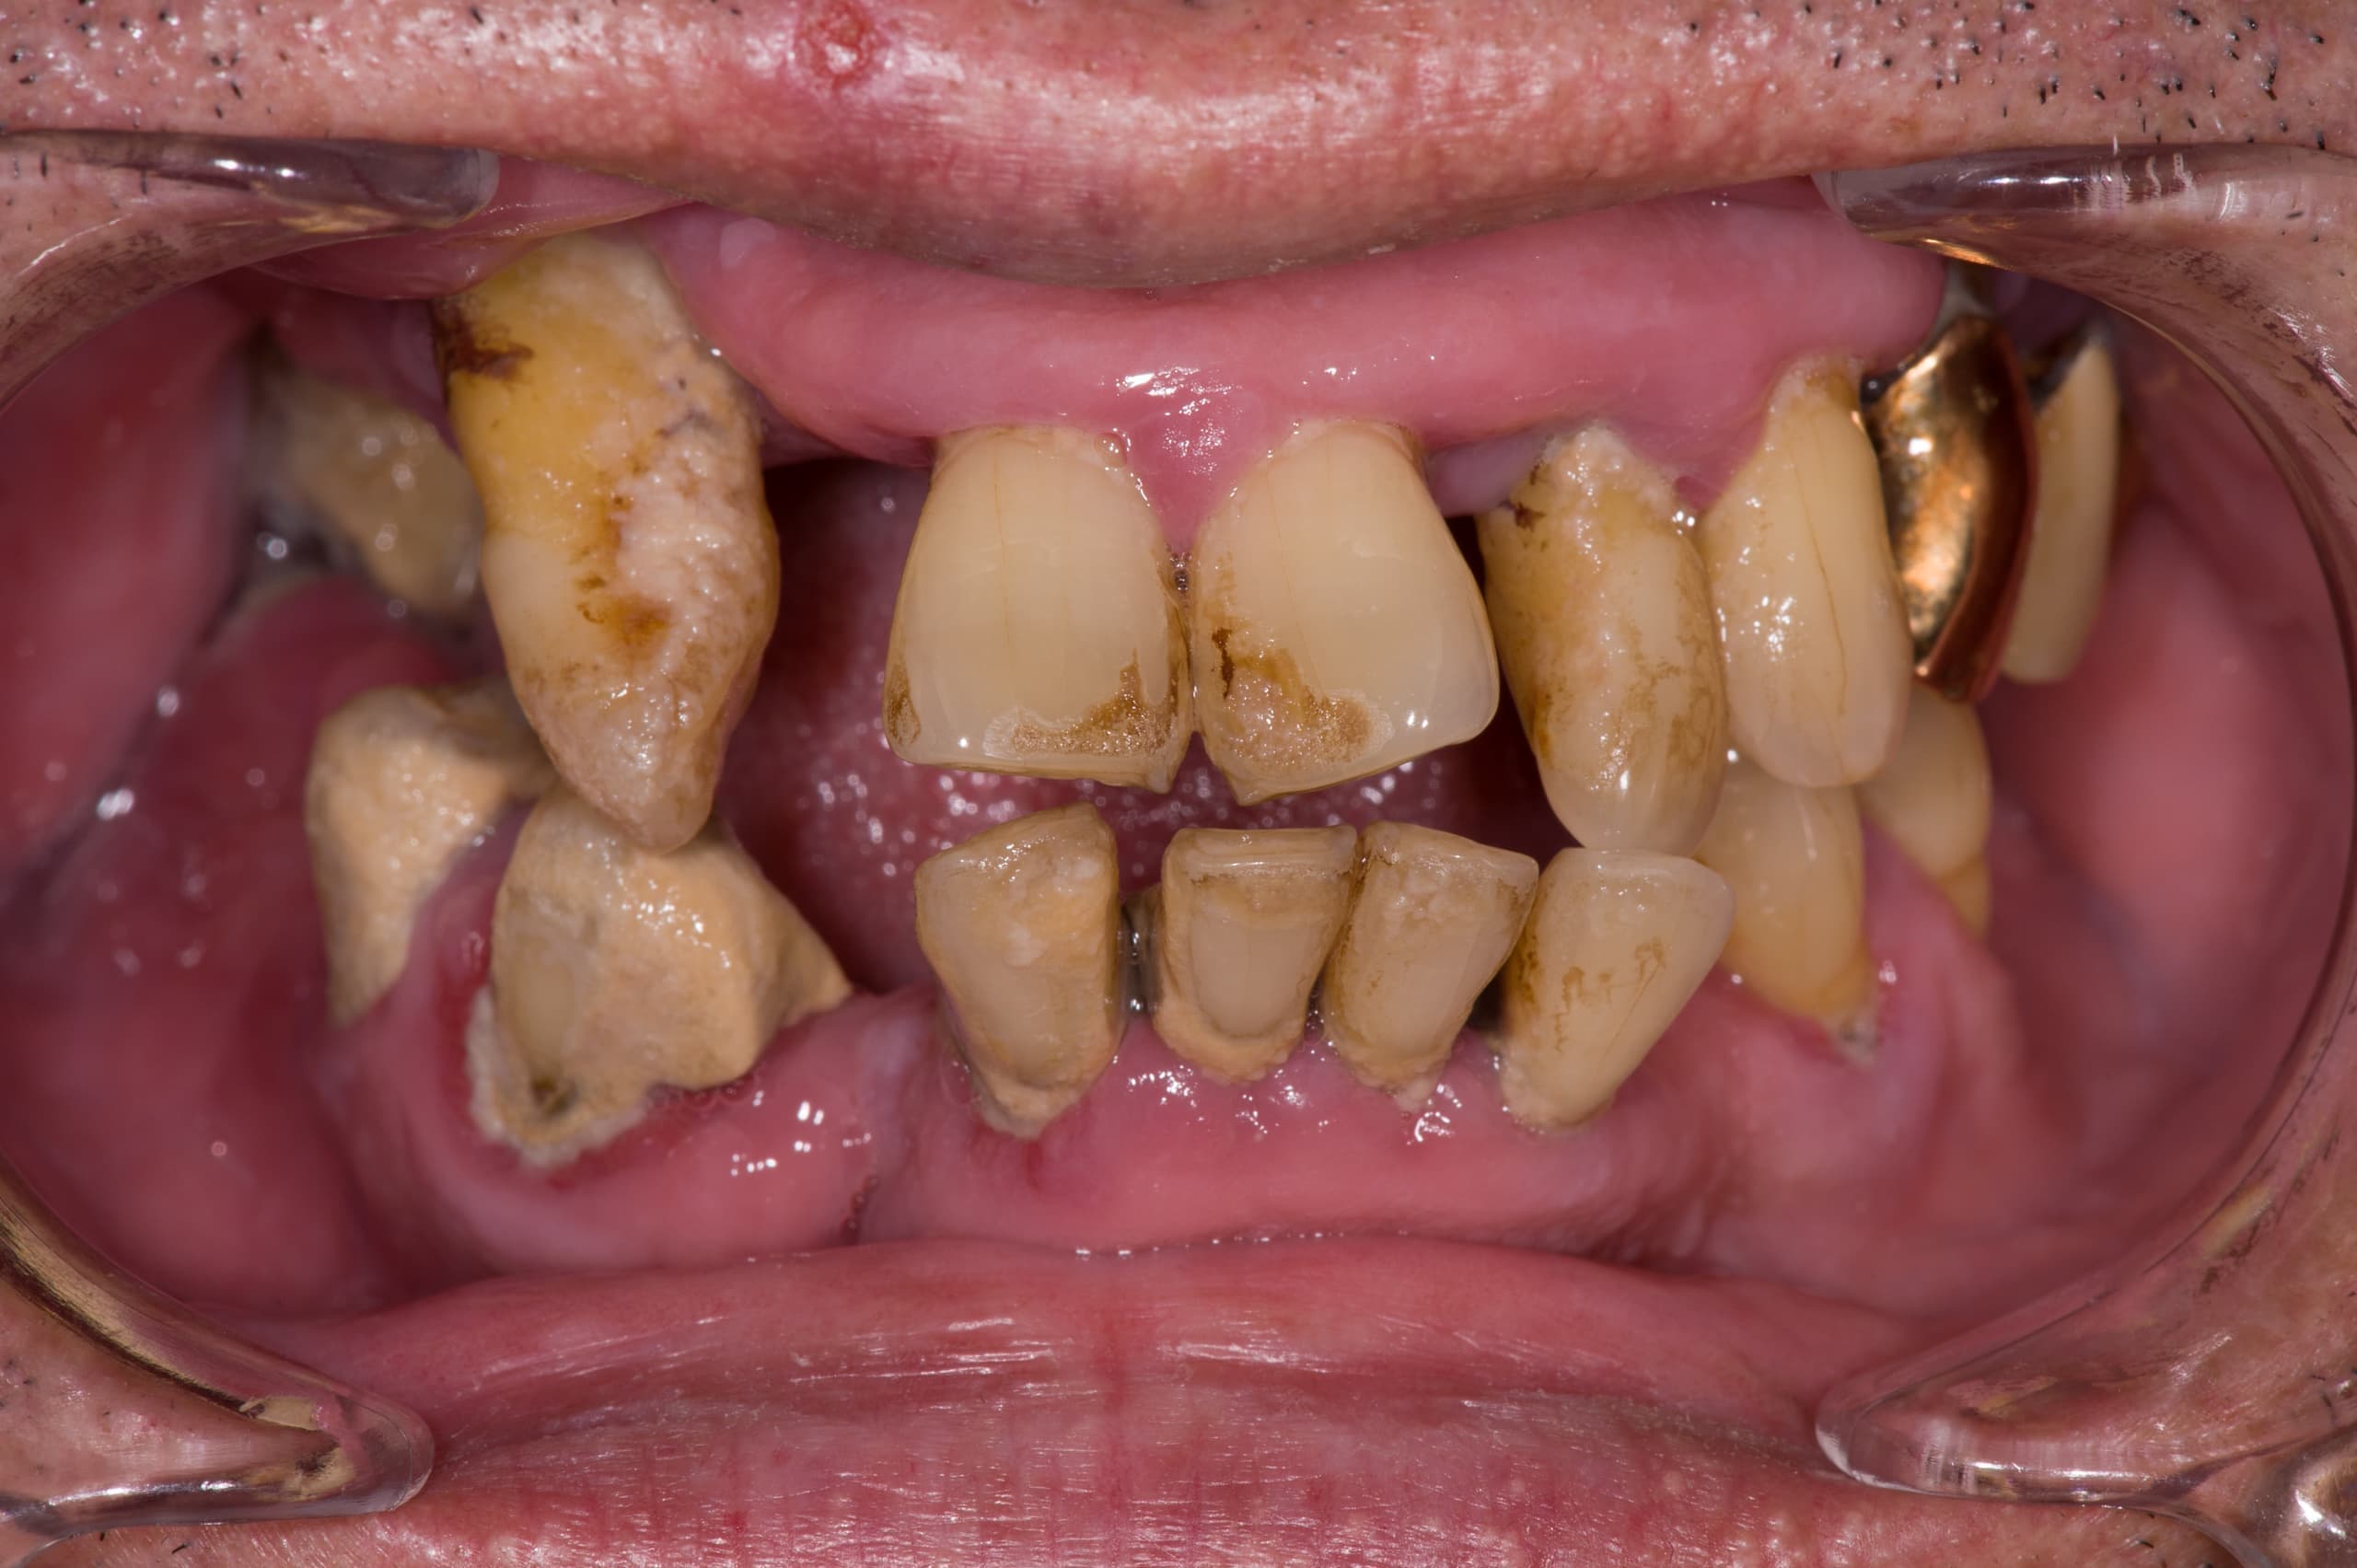

早期発見が重要です

小さな虫歯を放置してはいけません

他院では見逃してしまうケースもしっかり対応します

専門医ではないと対応できない症例もあります